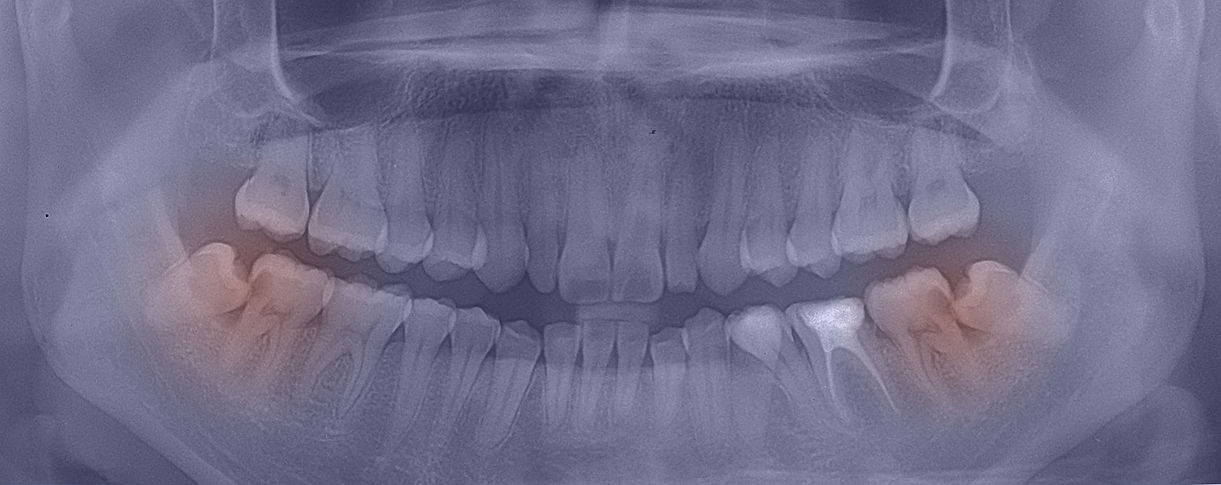

Caring & expert tooth extractions in Adelaide.

Having a tooth removed doesn't have to be painful or scary. At Adelaide Tooth Removals, we are highly experienced at removing wisdom and non-wisdom teeth and are dedicated to minimizing patient discomfort and anxiety. We offer treatments under local anaesthesia, oral sedation, IV sedation and general anaesthesia. General anaesthesia is delivered by an accredited specialist anaesthetist in an accredited day surgery or private hospital.

At Adelaide Tooth Removals, we are fully equipped, experienced and trained to diagnose and manage all the causes of toothaches.

We are one of the few practices with a dual-qualified dental surgeon who is not only experienced in oral surgery and tooth removal but also experienced in root canal treatments, dental restorations and crowns.